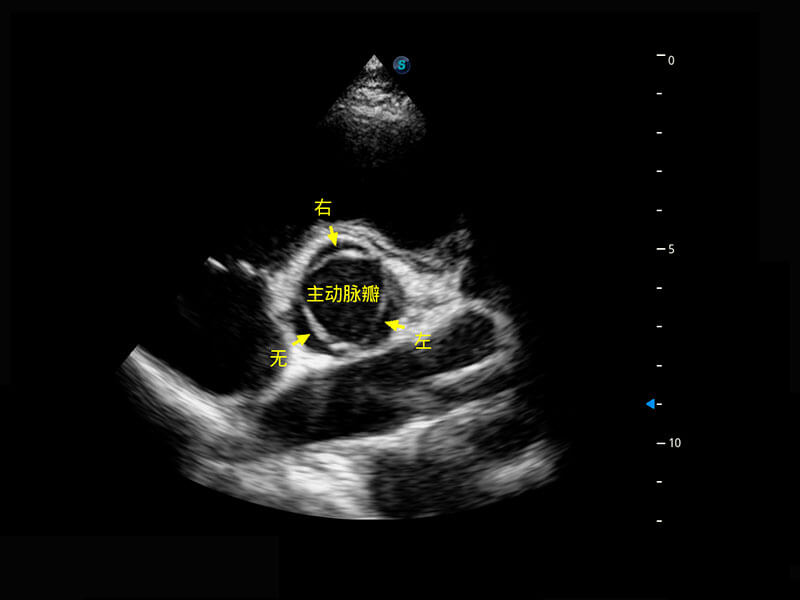

P60优异的图像质量搭载专科探头,在妇科基础疾病的诊断、卵泡生长的监测、输卵管通畅情况的判别等方面为您提供生殖应用方案。

腔内妇科-宫腔分离

腔内妇科-卵巢

腔内三维-宫内节育器

腔内三维-光影成像